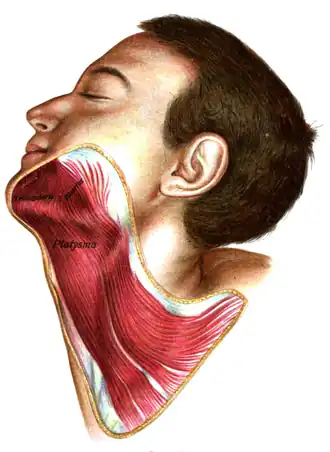

Platysma muscle

The platysma is visible, with skin removed. | |

The platysma muscle or platysma is a superficial muscle of the human neck that overlaps the sternocleidomastoid. It covers the anterior surface of the neck superficially. When it contracts, it produces a slight wrinkling of the neck, and a "bowstring" effect on either side of the neck.

The platysma muscle is a broad sheet of muscle arising from the fascia covering the upper parts of the pectoralis major muscle and deltoid muscle. Its fibers cross the clavicle, and proceed obliquely upward and medially along the side of the neck. This leaves the inferior part of the neck in the midline deficient of significant muscle cover.[3]

Fibres at the front of the muscle from the left and right sides intermingle together below and behind the mandibular symphysis, the junction where the two lateral halves of the mandible are fused at an early period of life (although not a true symphysis). Fibres at the back of the muscle cross the mandible, some being inserted into the bone below the oblique line, others into the skin and subcutaneous tissue of the lower part of the face. Many of these fibers blend with the muscles about the angle and lower part of the mouth.[3]

Sometimes fibers can be traced to the zygomaticus major muscle, or to the margin of the orbicularis oris muscle. Beneath the platysma, the external jugular vein descends from the angle of the mandible to the clavicle.[4]

Platysma is visible at bottom, in neck

Platysma is visible at bottom, in neck -

Platysma

Platysma